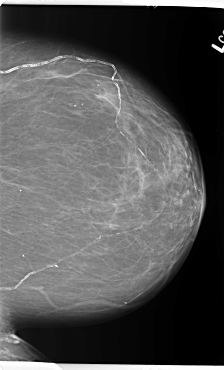

B_3141_1.LEFT_CC

LEFT_CC LINES 5912 PIXELS_PER_LINE 3584 BITS_PER_PIXEL 12 RESOLUTION 50 NON_OVERLAY